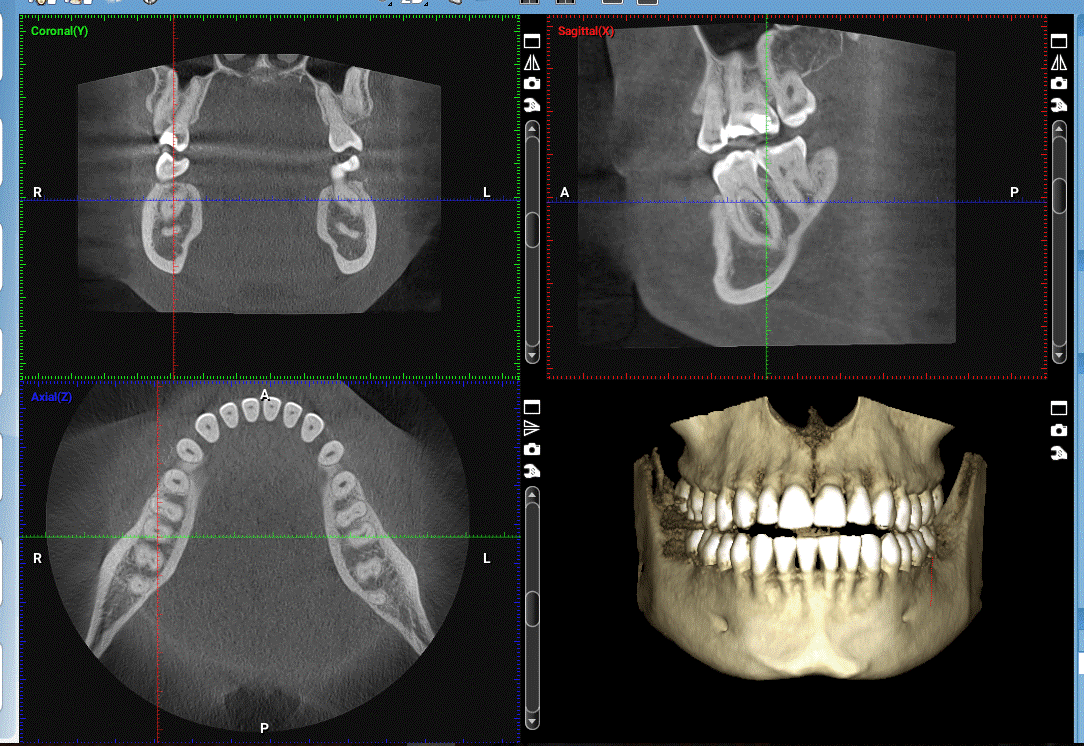

دانشگاه علوم پزشکی گیلان، کنفرانس علمی یک روزه تحت عنوان «تجویز و تفسیر رادیوگرافی و کاربردهایCBCT» را در تاریخ 20 مهرماه جاری برگزار می کند.

جامعه علمی دندانپزشکی ایران شعبه گیلان، کنفرانس علمی یک روزه تحت عنوان «تجویز و تفسیر رادیوگرافی و کاربردهایCBCT» دارای امتیاز آموزش مداوم، با حضور تخصص های (رادیولوژی دهان و فک و صورت، بیماریهای دهان وفک و صورت، پروتزهای دندانی، دندانپزشکی ترمیمی، جراحی دهان و فک وصورت، بیماریهای دهان و تشخیص، اندودانتیکس، پریودانتیکس، آسیب شناسی فک وصورت، رادیولوژی دندان و فک و صورت، پریودانتیکس، ارتودانتیکس، اندودانتیکس، دندانپزشکی کودکان)، و دندانپزشکان عمومی مقطع دکترای حرفه ای، از ساعت 8 لغایت 14:30 روز پنجشنبه مورخ 20 مهرماه سال 1403 در سالن آمفی تئاتر مجموعه قصر بازی رشت واقع در کیلومتر 5 جاده رشت انزلی برگزار می کند.